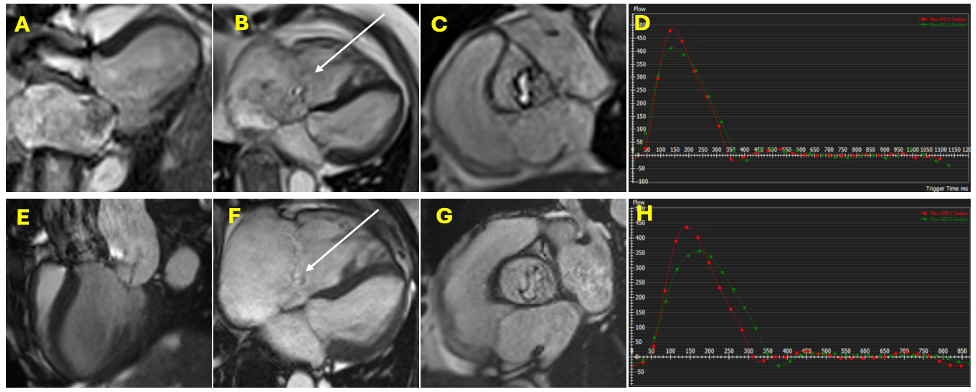

Bland-Altman and Scatter Plots of Aortic and Pulmonary Forward Flow and Regurgitant Volume